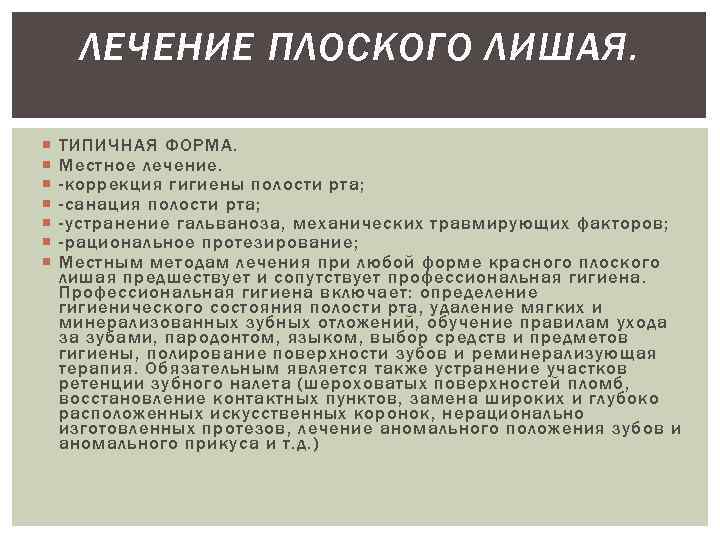

Фото Красного Плоского

Фото Красного Плоского 103 фото